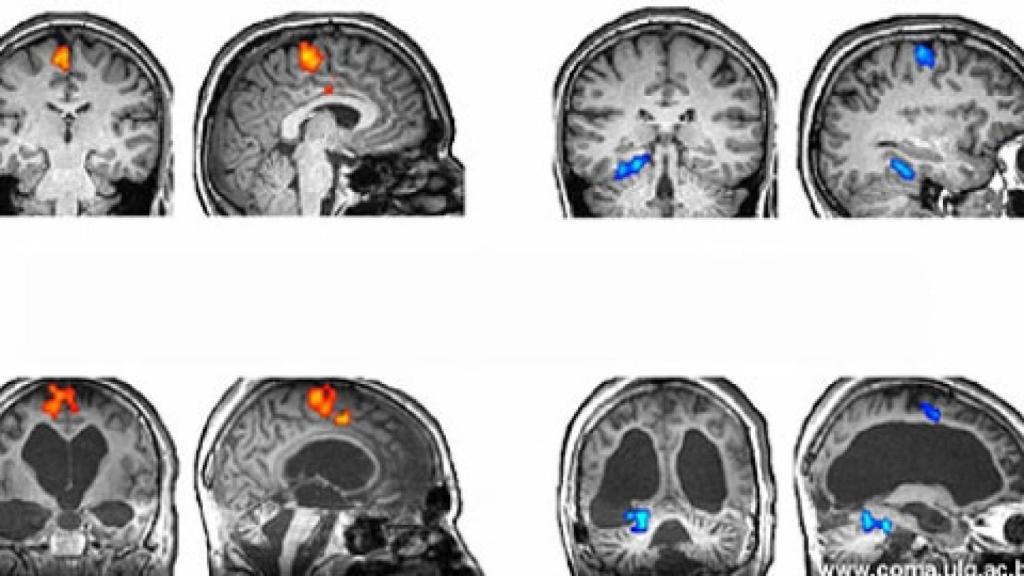

Increíblemente, el paciente le proporciono respuestas. Hubo un cambio en el flujo sanguíneo a ciertas partes del cerebro del hombre, un hecho que convenció al Dr. Owen de que el paciente estaba consciente y era capaz de comunicarse. Era la primera vez que alguien había intercambiado información con un paciente en estado vegetativo.